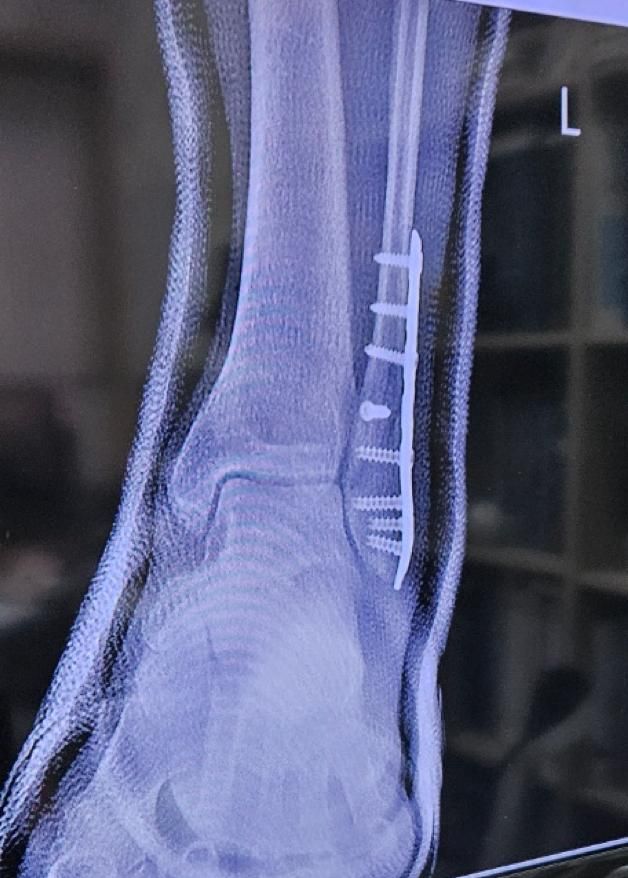

• 1번 째 사진

엑스레이 영상으로 추정컨데, 수상 당시 골절이 심각한 상태였을거라 예상됩니다.

그만큼의 골절이 생겼다면 신경 손상이 동반되었을 가능성이 높고, 이에 대한 회복에는 상당 시간이 소요됩니다.

깁스를 하다가 제거한지 얼마 안되었다면 아직은 회복하는 과정에서 나타나는 증상일거라 사료됩니다.

그러나 이는 골절과 수술 후 생길 수 있는 일반적인 상황에 대해 말씀드리는 바이며, 질문자께서 언급하신 중대 합병증의 가능성도 항상 고려해야 하므로 병원에서 정기적인 관찰과 치료가 유지되어야 합니다.